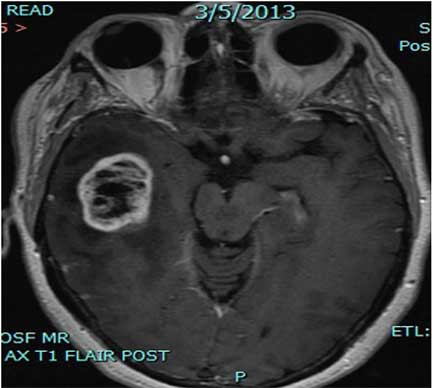

13+ Brain Tumor Survivor Stories Glioblastoma Multiforme PNG. Www.braintumor.org > your voice > share your story on november 28th, 2015, my father was diagnosed with glioblastoma multiforme stage four brain cancer. Glioblastoma multiforme (gbm) is the most common and aggressive type of primary brain tumor.

It is also known as glioblastoma multiforme. A glioma is a type of brain tumor that grows from glial cells. This time, the tumor was still very small, so they zapped it with the gamma knife.

Glioblastoma also known as glioblastoma multiforme or with the acronym gbm is the most common and most aggressive among brain cancers. Bill asenjo, a survivor of six brain tumor surgeries, is completing his phd dissertation (alternative medicine and disability) at the university of iowa. The changed or abnormal cells often grow to form a. So the idea with this video is to tell.